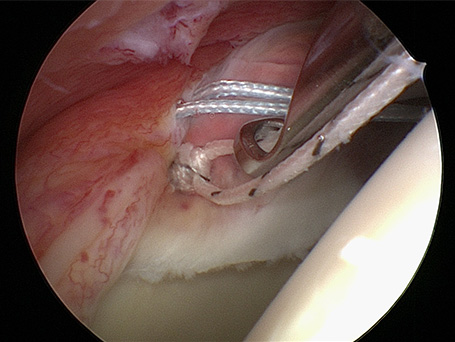

69-jähriger Patient mit linkseitiger Schulterluxationsverletzung. Bei älteren Patienten kommt es im Rahmen der Schulterverrenkungen häufiger zu Sehnenabrissen am Oberarmkopf. Trotz der Einrichtung des Gelenkes kann der Arm nicht wieder gut bewegt werden. Erst die operative, in diesem Falle rein arthroskopische Rekonstruktion der Sehnen und deren Einheilen ist eine Schultergelenksbewegung wieder gut möglich.

Neben der konservativen Behandlung bieten wir operativ sowohl arthroskopische als auch offene Stabilisationsoperationen an. Das Spektrum der operativen Behandlung reicht von reinen Kapselstabilisationsoperationen (Bankartrepair) über akute knöcherne Kapsellabrumabrisse bis hin zu veralteten komplexeren Instabilitätsoperationen mit Defektaufbau an der Schultergelenkspfanne bei fehlendem Knochen.